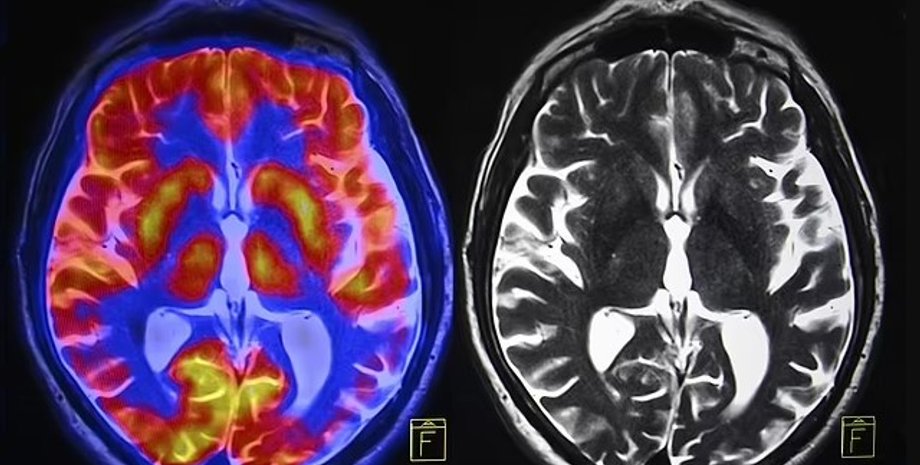

Ученые уже давно спорят о том, проявляются ли половые различия в мозге | Фото: Shutterstock

мозг мужчины женщины

Какие части мозга наиболее важны для различения мужчин и женщин: полосатое тело и области, участвующие в сети режима по умолчанию и лимбической сети

Фото: PNAS